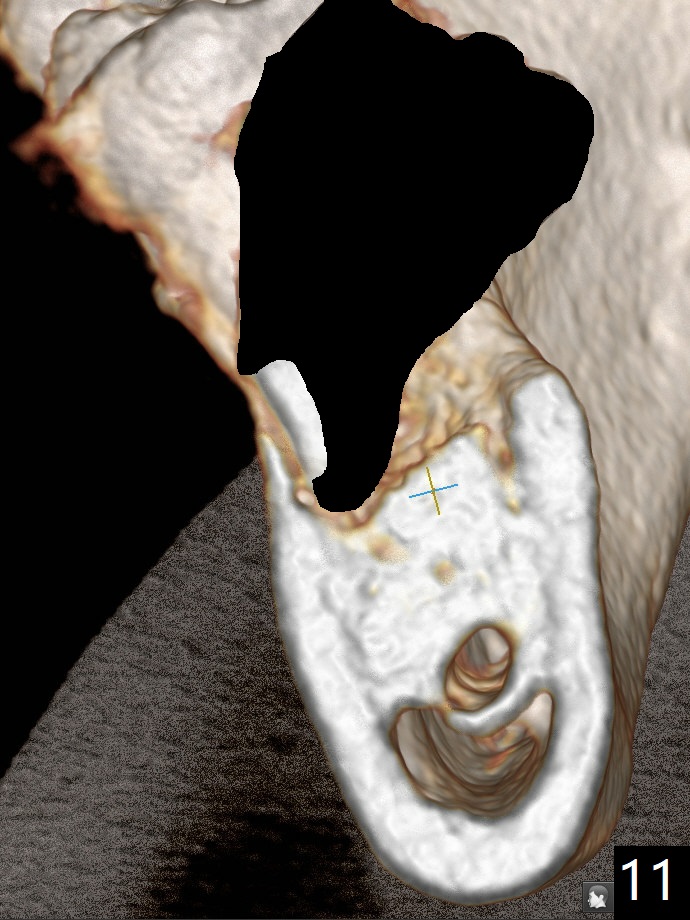

A 44-year-old woman has severe chronic periodontitis. The tooth #18 is nonsalvageable (Fig.1). To avoid distal end guide, do not remove the 3rd molar in the lab. While a 5x7.3 mm implant is long for the site (Fig.2), a 5.5x5.5 mm one seems to be a better option (Fig.3). The latter could be 1 mm more coronal. The last drill (5.0 mm) and cortical tap will be used free hand. #17 will be extracted after implantation. Since the patient is reluctant to have #16 to be extracted, place #18 implant ~ 1-2 mm more distal so that the implant crown will have some occlusal contact with #16. Prepare IS extra wide kit. Or use a 8/7 mm trephine bur to harvest cortical bone from the ramus. Drill a hole for fixation screw before removing the onlay graft. Keep the 3rd molar if possible. Prepare Tatum spacers to measure the size of #18 socket opening. In fact, the lab is able to place a 5x7.3 mm implant with 2 thread exposure buccal. Prepare sticky bone and PRFx2 to prevent periimplantitis. Soak one O-ring in case of having to extend osteotomy by .5 mm (next longer drill (1.5 mm) - 1 mm (O-ring)). For socket shield at #18 (Fig.6 *), section the tooth horizontal with a new surgical fissure bur (Fig.4 black area), use an end-cutting bur to remove buccal edge of the root (Fig.5 red area) and finally remove the lingual portion of the root (Fig.6 pink). Insert 4.5x10 mm dummy implant to determine whether the final implant 5x7.3 mm (bottom of the 1st line) will probably contact the shield. Buccal view of the lingually inclined 2nd molar (Fig.7). After removal of the crown of the 2nd molar (Fig.8 occlusal view), the lingual portion of the root is resected (Fig.9 black area). CT coronal sections show socket shield formation (Fig.10,11).